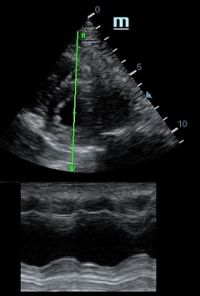

TAPSE - показатель амплитуды движения латеральной части кольца трикуспидального клапана, позволяет количественно и быстро оценить систолическую функцию правого желудочка, норма которого составляет более 17 мм. Главным условием является проведение линии М-режима параллельно стенке правого желудочка в апикальном четырех камерном сечении, что легко достигается при Free Xros.

MAPSE - амплитуда движения латерального кольца митрального клапана, позволяет рассчитать фракцию выброса по формуле EF = 4.8 × MAPSE (mm) + 5.8, очень быстрый и гораздо более точный («прародитель Strain») метод чем широко распространенный метод Teicholtz. В современных приборах можно легко добавить свою формулу при отсутствии ее в стандартном калькуляторе. Главным условием является проведение линии М-режима параллельно стенке левого желудочка в апикальном четырехкамерном сечении, что легко достигается при использовании функции Free Xros.